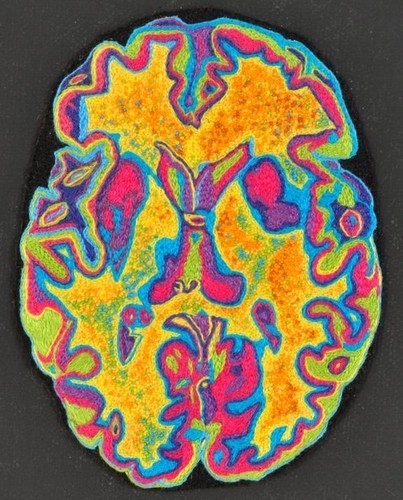

הפרעת הספקטרום האוטיסטי (ASD) היא הפרעה התפתחותית עצבית ונפשית, המשפיעה על קישוריות המוח ועיבוד מידע. אנשים עם ASD מתקשים לעתים קרובות באינטראקציה חברתית, תקשורת והתנהגויות מגבילות החוזרות על עצמן. טיפול נוירופידבק להפרעת הספקטרום האוטיסטי משפר ומחזק את דפוסי גלי המוח של המטופל כדי להשיג איזון אופטימלי יותר של גלי מוח איטיים ומהירים וקישוריות במוח. שינויים אלו יסייעו לחולים עם אוטיזם לתפקד בצורה יעילה יותר.

בבסיס הפתולוגיה וההטרוגניות המגוונת של ASD עומדת אינטראקציה מורכבת של גנטיקה, חשיפות סביבתיות ופתופיזיולוגיות מערכתיות, שכולן הראו כמשפיעות על קישוריות המוח ועיבוד המידע (Holiga et al., 2019; Cheroni et al., 2020; Carroll et al., 2021; Panisi et al., 2021).

אנו משתמשים במיפוי מוחי qEEG כדי לאתר אילו רשתות או מעגלים עצביים במוח פועלים בצורה לא נכונה או לא מתפקדים, ובכך גורמים או תורמים לתסמינים האוטיסטיים של המטופל.